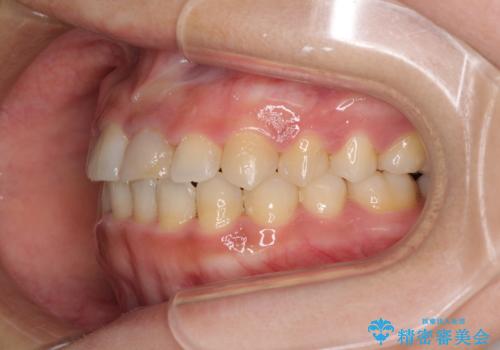

前歯の反対咬合 非抜歯のワイヤー矯正

- 前歯のでこぼこを気にして来院された患者様です。

マウスピース矯正の自己管理が面倒くさいことと、治療を早く終わらせたいとのことで、目立ちにくいワイヤー矯正にて歯列を整えることとしました。

1年半はかかると思っていた治療期間ですが、反対咬合となっている前歯が思いの外早く動き、僅か9ヶ月で終了させることができました。

前歯を気にせず笑えるようになり、患者様には大変満足していただきました。